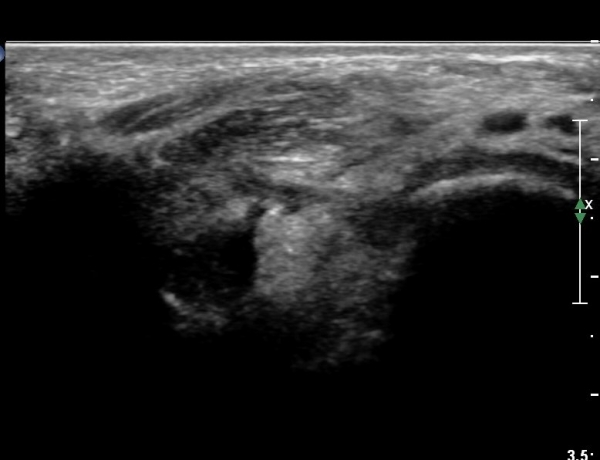

¹ß¸ñ °üÀý Á¾´Ü¸é°Ë»ç¿¡¼­ °æ¹ÌÇÑ °üÀý³» ºÎÁ¾À» º¸ÀÓ(»çÁø 1).